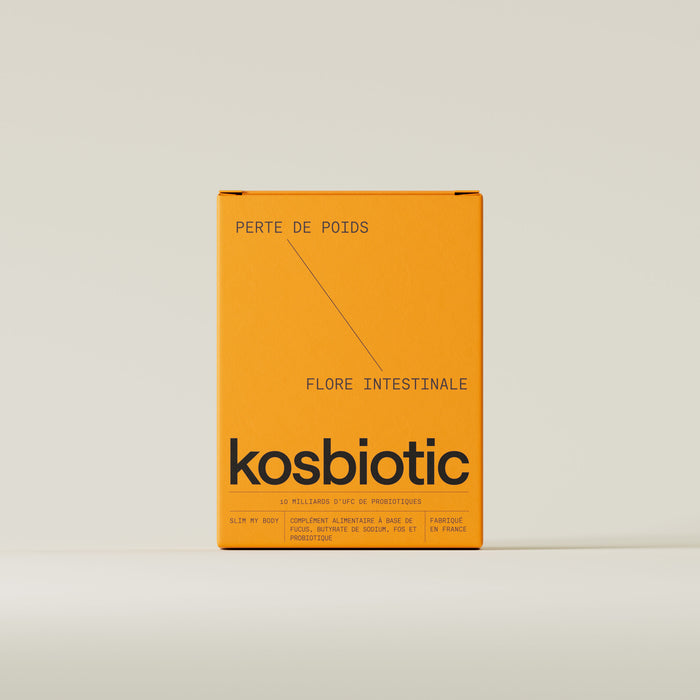

Ventre plat

Perte de poids

Flore intestinale

La nouvelle formule probiotique Slim My Body réunit une souche probiotique brevetée, la Bifidobacterium lactis B420®, l'algue brune Fucus Vesiculous, de la caféine, du chrome, ainsi que des prébiotiques et des postbiotiques.

Cette souche probiotique d'exception présente dans Slim My Body, a fait l’objet d’une étude clinique in vivo concluante sur des personnes en situation de surpoids.

Slim My Body vous retransmet le dosage qui a prouvé ses bienfaits lors de cette étude clinique :

- 4% de masse graisseuse abdominale en moyenne

- 2,4% de tour de taille en moyenne

Pour compléter l'action de la souche B420®, et améliorer ses résultats, nos chercheurs ont sélectionné une algue brune au pouvoir amincissant unique : le Fucus.

Le Fucus est une merveille 100% naturelle provenant des océans, au service de votre santé et de votre perte de poids dont les vertus sont :

- Stimule naturellement la perte de poids

- Augmente le sentiment de satiété

En accélérant naturellement le métabolisme et en diminuant la masse graisseuse, notre formule Slim My Body engendre une perte de poids,

une réduction visible de la cellulite, un affinement du ventre, et une réduction des ballonnements.

L’ étude clinique in vivo sur la souche Bifidobacterium lactis B420®, a été réalisée sur 225 personnes, en situation de surpoids.

La formule Slim My Body vous retransmet le dosage spécifique qui a été testé durant cette étude clinique.

Notre philosophie est de réunir la recherche de pointe sur les probiotiques, avec des plantes ou des algues à l’usage ancestral.

Voilà pourquoi nos chercheurs ont choisi une algue brune, le Fucus Vesiculosus.

- 100% naturel

- Stimule la perte de poids.

- Augmente le sentiment de satiété

- Contient des pré et postbiotiques